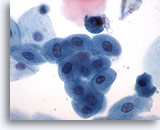

Urine obtenue par cathétérisme, résultat négatif

Les groupes de cellules sont souvent détruits par le cathétérisme.

20x